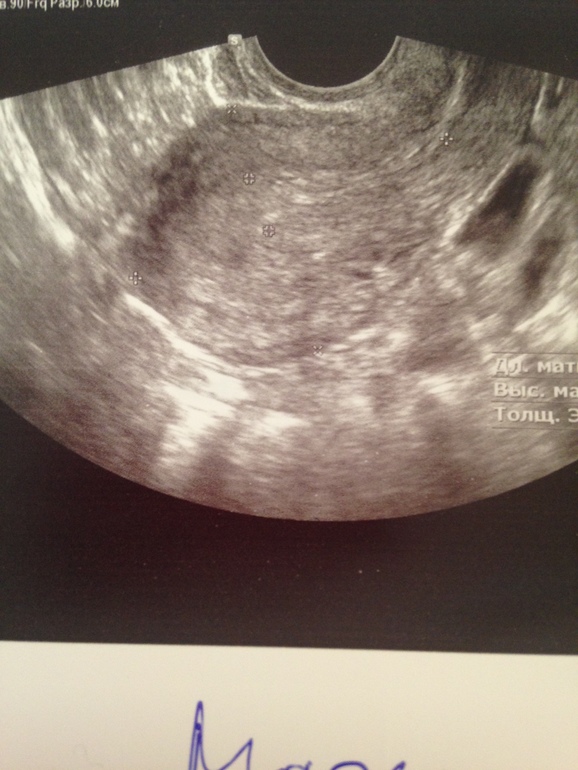

Добрый день,девочки.Дано:35ДЦ,задержка уже ну как минимум 3-5 дней...Тесты отрицательные ,на 23 ДЦ нашли в эндике включение 0,34 мм.Овуляцию чувствовала на 15-17 дц (точно не помню но не раньше ,не позже)резкая боль в ЛЯ,чуть розово-красных выд-ий.Сегодня УЗИ :Эндик 7мм(однородный)в ПЯ ЖТ 13мм??На 90%ЖТ как сказал врач.А мне вот не кажется,что это похоже на ЖТ,но я не врач,хз.В ЛЯ только фоллики..И никакого образования в Эндик нету(специально не сказала ,что там что-то находили,для чистоты эксперимента)Но когда будут М не сказали,ЖТ или нет не понятно.Да и чувствовала я 💯 процентов слева!!!Прилагаю фото,где два снимка -это сегодня ПЯ и ЛЯ,где один с точкой это включение -на 23 дц,ну и последний сегодня эндик .Как думаете,ЖТ???

А мне от этого,что я и не жду беременность,потому что мы предохраняемся))Хоть и ППА,но все же осечек небыло ...А вот циклы мне по 50 дней точно не нужны.Да и причём тут Б?Вопрос мой в том,похоже это на ЖТ или это фоллик!Т.к.врач сам не дал 100% ,что это Жт.Если ЖТ,то буду ждать М,а если нет,то дюфастон мне в помощь!